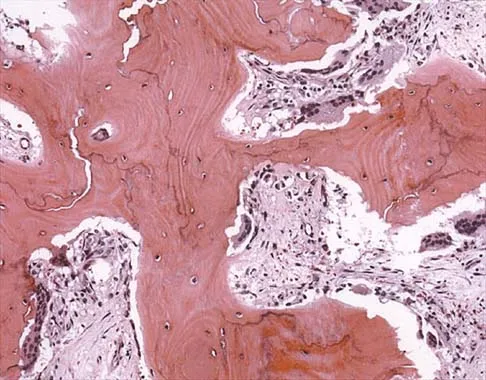

Figure 26a shows the radiograph of a 55-year-old woman who has pain in her right leg after falling. Laboratory studies reveal an elevated alkaline phosphatase level. A biopsy specimen from the proximal tibia is shown in Figure 26b. What is the most likely diagnosis?

Explanation

Paget's disease of bone is a metabolic disorder of bone remodeling. The normally coupled process of bone resorption and deposition is lost, resulting in excessive localized bone resorption and compensatory increased bone formation. Pagetic bone tends to be more brittle; therefore, it is susceptible to pathologic fractures and subsequent deformities. Lander PH, Hadjipavlou AG: A dynamic classification of Paget's disease. J Bone Joint Surg Br 1986;68:431-438.